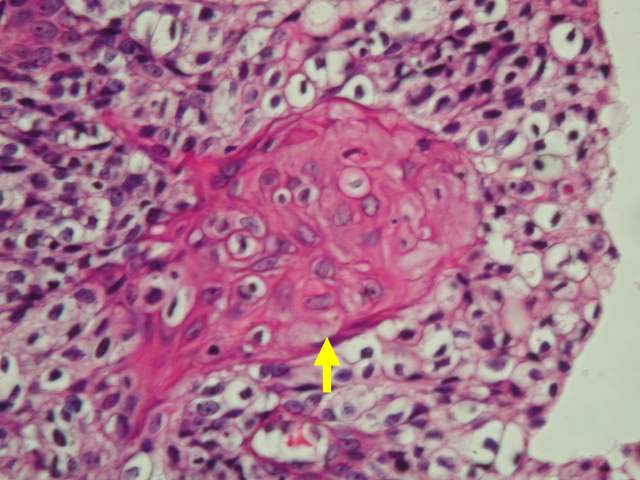

(Figure 1) Transitional cell carcinoma of ureter with papillary tumor in the mucosa of the

ureter (arrow). The carcinoma dose not invade the underlying stroma.